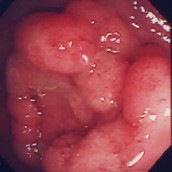

急性胃炎:

心窩部痛、食欲不振、吐き気を訴えて来院。内視鏡検査を施行すると、前庭部に線状のびらんを認め、急性胃炎の所見です。整形外科から処方された鎮痛剤が原因でした。抗潰瘍剤、粘膜保護剤の内服で症状は速やかに消失しました。